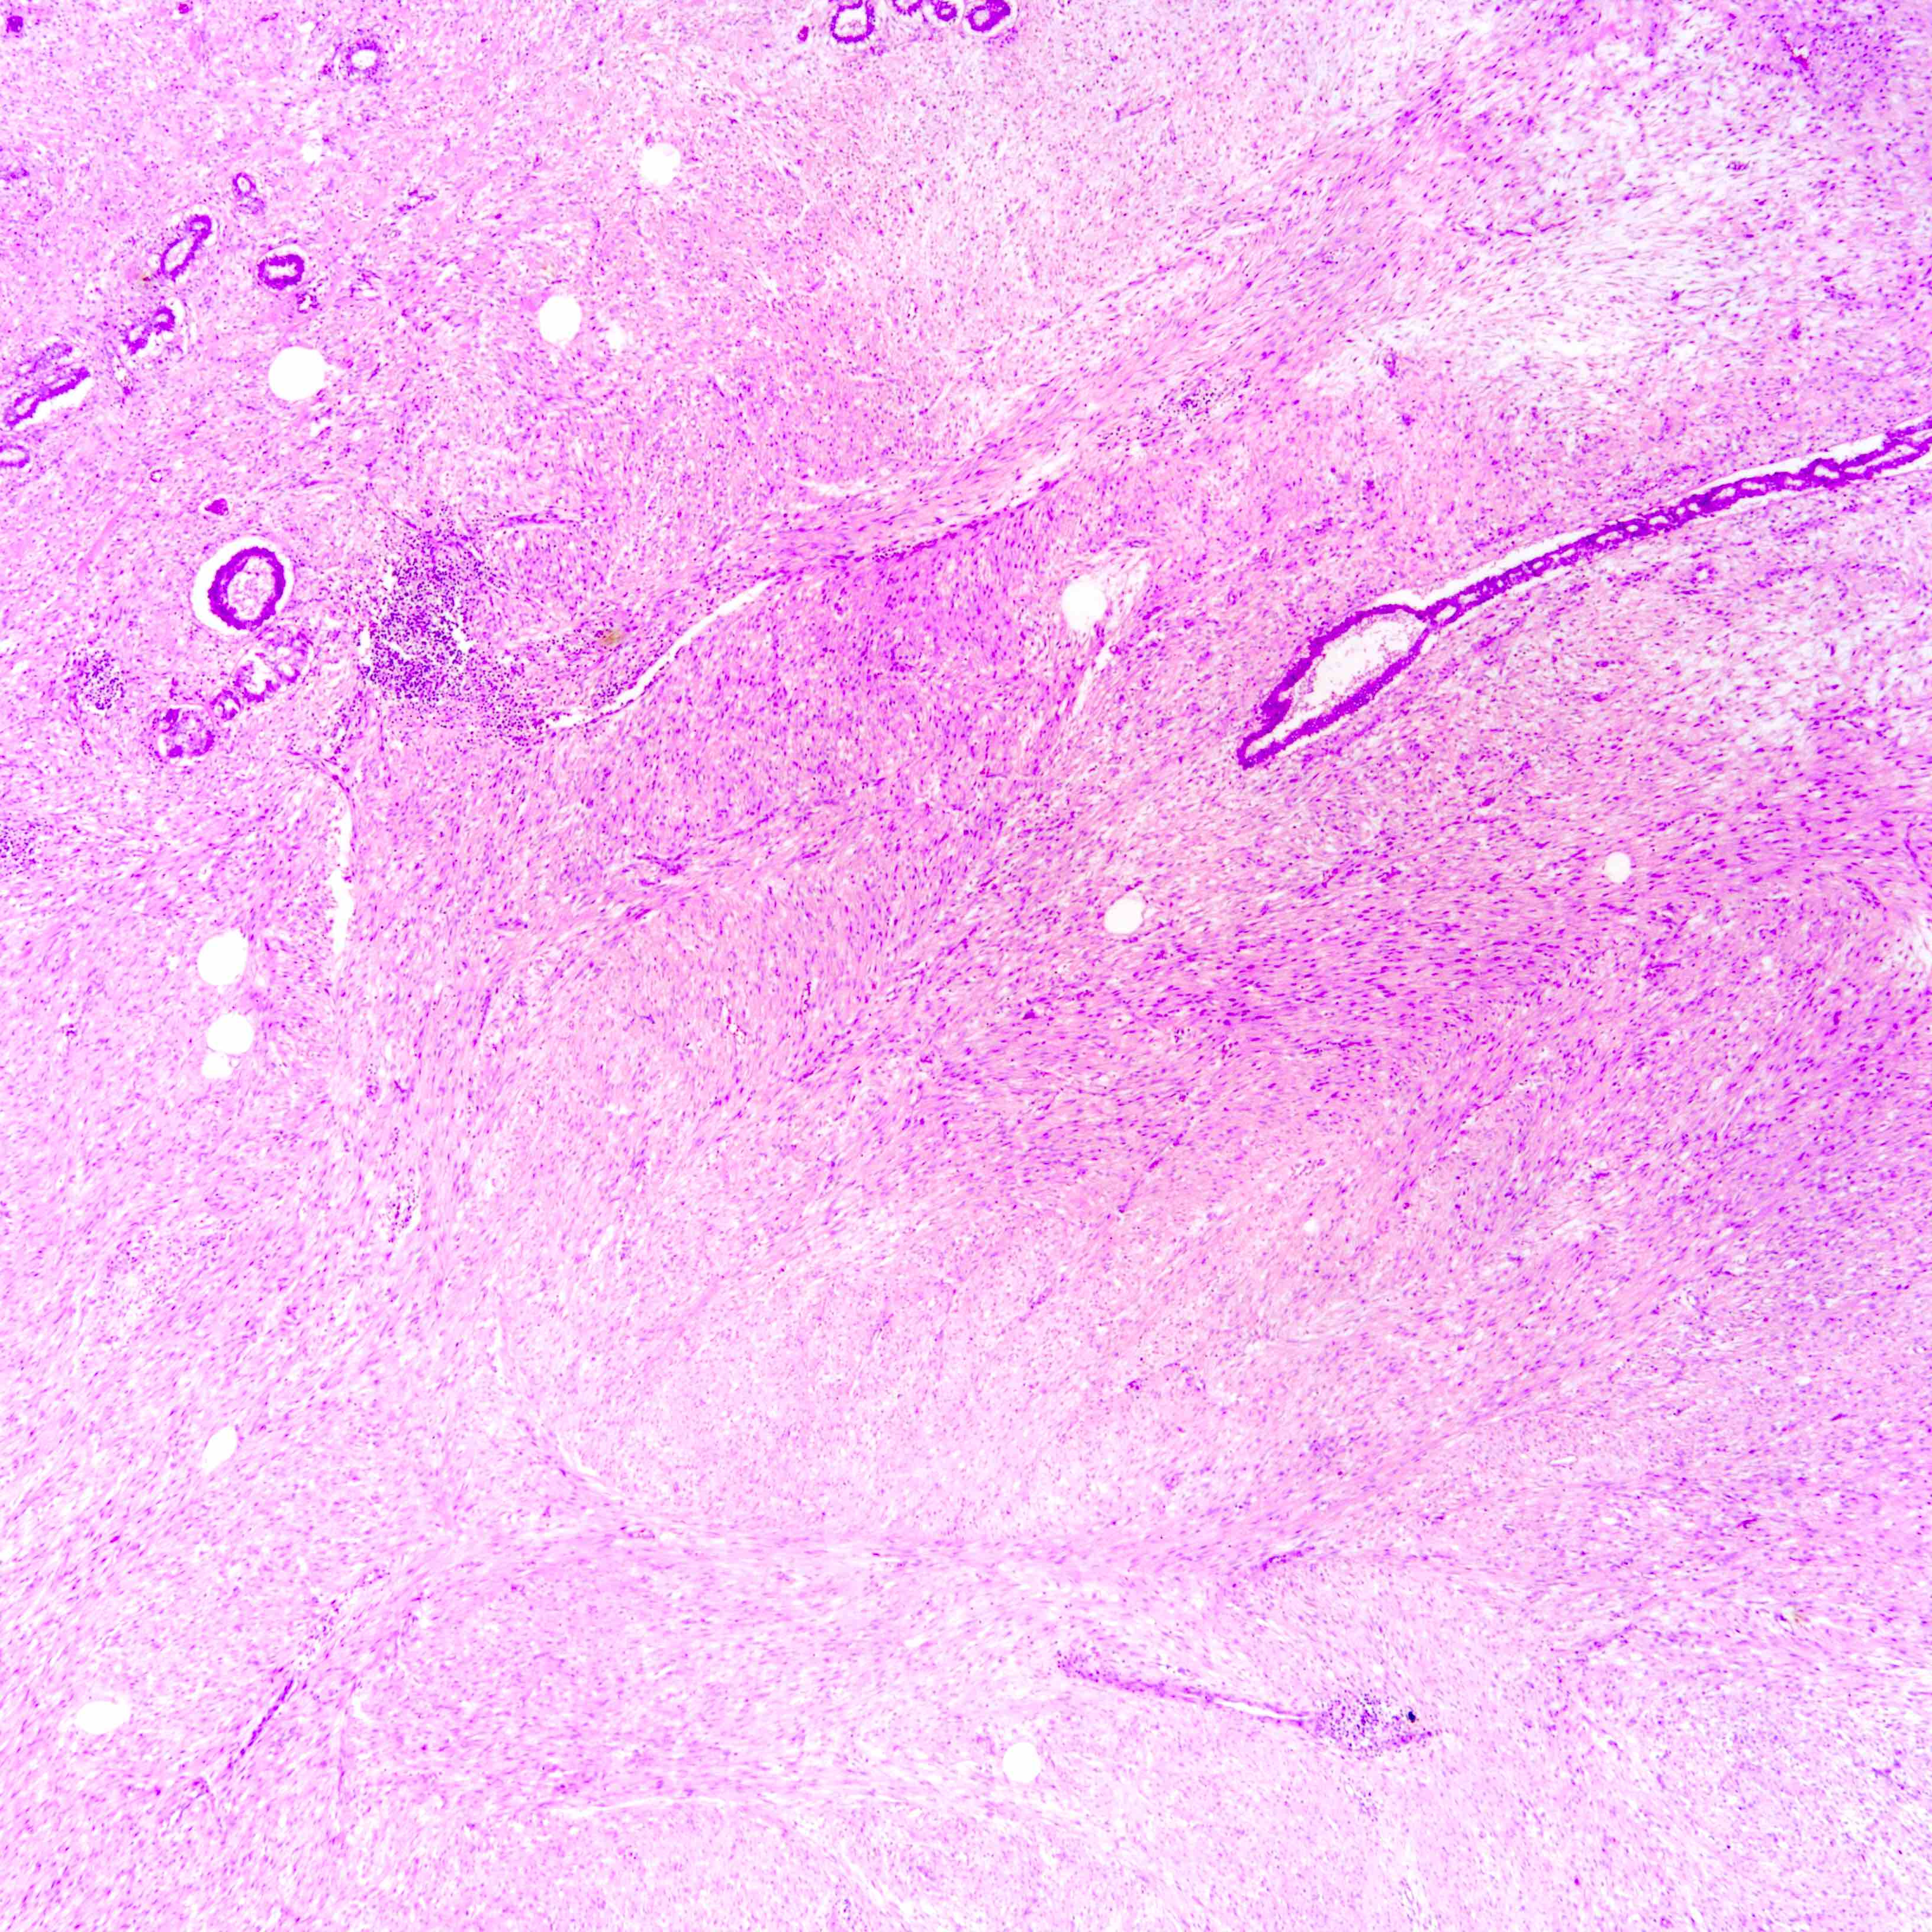

- Graded into benign, borderline and malignant histologic grades

Benign Borderline Malignant Stromal atypia Mild Moderate Marked Stromal cellularity Mildly increased, can be focal Moderately increased, can be focal Markedly and diffusely increased Stromal overgrowth* Absent Absent or very focal Present Mitotic count < 5/10 HPF or < 2.5/mm² 5 - 9/10 HPF or 2.5 - < 5/mm² ≥ 10/10 HPF or ≥ 5/mm² Tumor border Well defined Well defined or focally permeative Diffusely permeative Malignant heterologous elements Absent Absent Presence directly upgrades to malignant category** -

Microscopic (histologic) images

Contributed by Joshua J.X. Li, M.B.Ch.B. and Gary M. Tse, M.B.B.S.

Borderline phyllodes tumor

Malignant phyllodes tumor